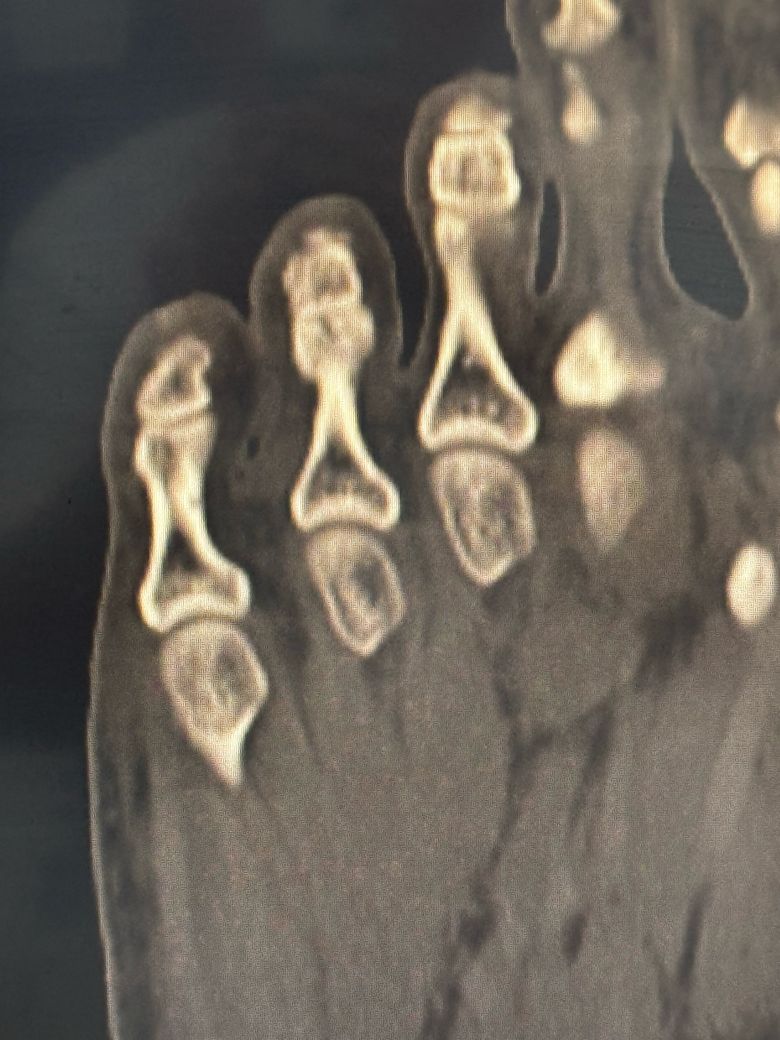

• 4번 째 사진

이미지상 발가라 뼈에 금이 가거나 골절 소견이 있어보이지만 정확한 수술 여부는 골절의 위치 각도 뼈 어긋남 여부에 따라 다릅니다.

통증이 크지 않고 전위가 적으면 반깁스나 테이핑으로 4~6주 고정 후 자연 치유를 기다릴 수 있습니다. 지금은 무리하지 말고 정형외과에서 1~2주 간격으로 엑스레이 추적 검사를 받아 회복 경과를 확인하세요!

발가락 골절로 인한 수술 관련해서 질문을 주셨는데 골절의 정도 및 어긋남 정도 그리고 증상에 따라 수술 여부가 결정될 수 있으며 발가락이 휘어져 보이거나 뼈가 많이 어긋나거나 관절에 영향을 주는 골절 같은 경우 수술이 필요할 수 있습니다.